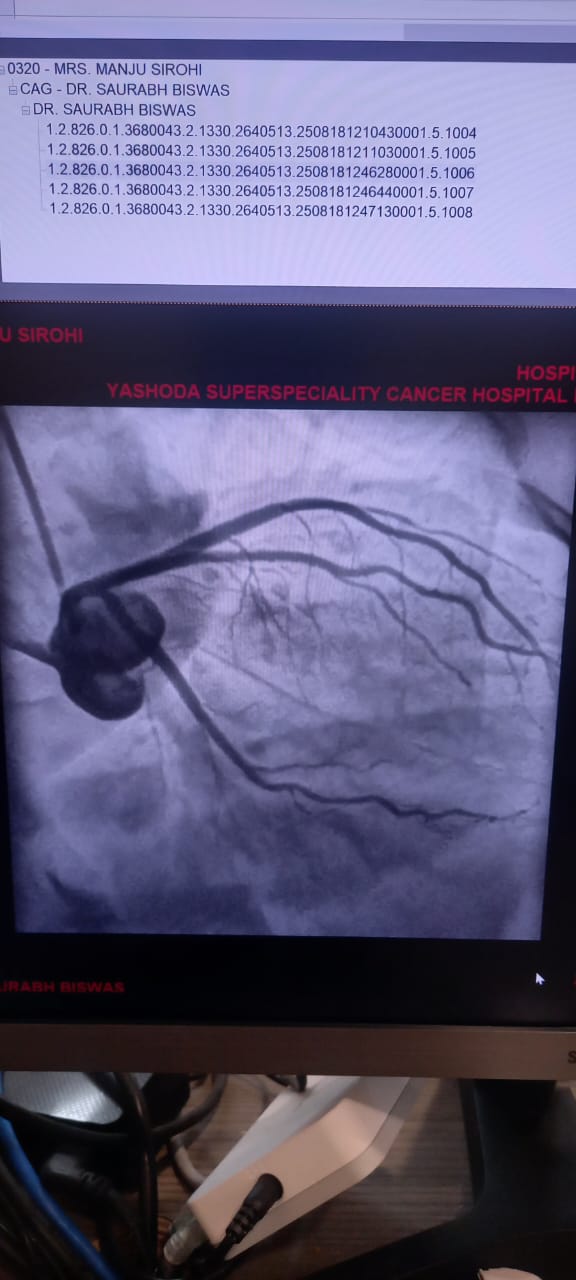

Angiography / Cardiac Cath

Angiography, also known as Cardiac Catheterization, is a minimally invasive procedure used to diagnose heart conditions. It provides detailed images of the heart's blood vessels, helping doctors detect blockages or narrowing.

Once it reaches the heart, a contrast dye is injected. The dye makes the coronary arteries visible on an X-ray screen, revealing any blockages, plaque buildup, or structural issues.

• Coronary Angiography: This is the most common type. It evaluates the coronary arteries for blockages or narrowing.

• If necessary, angioplasty or stenting may be done immediately